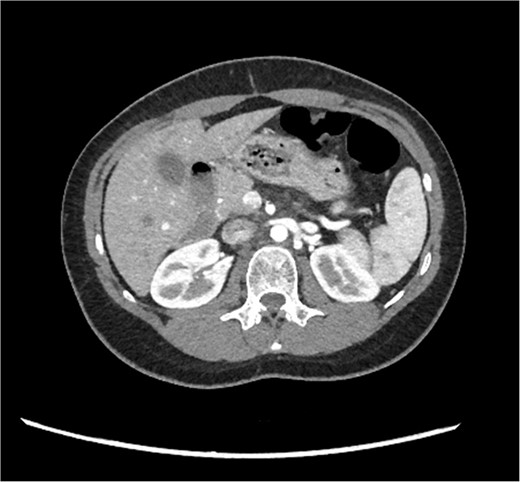

A 29-year-old female, with a past medical history of asthma and anxiety, presented to A&E Department at Mater Dei Hospital in view of a 2-day history of worsening right-sided colicky flank pain that radiated down to the right iliac fossa. Pain relief, including paracetamol and NSAIDS, alleviated her symptoms temporarily; however, pain recurred after a few hours. At A&E, patient’s parameters were noted to be stable throughout the review. On examination, the patient’s abdomen was noted to be soft with tenderness over the right flank. No guarding was noted, and renal punch was negative bilaterally. Blood investigations were all within normal limits, and urinalysis was normal. In view of the examination findings, a computed tomography (CT) of the kidney, ureters, and bladder was ordered, which noted an enlarged pancreatic head measuring 3 cm in diameter with noted upstream atrophic changes in the body and tail with fat stranding; prominent mesenteric lymph nodes were also noted. Based on the previous CT findings, a contrast CT of the pancreas was ordered, which revealed that the body and tail of the pancreas were absent; however, the pancreatic head was noted to be enlarged. This can be seen in Figs 1 and 2. Prominent lymph nodes with ground glass changes in the mesenteric fat were noted. CT pancreas therefore confirmed the diagnosis of dorsal agenesis of the pancreas. The patient was discharged home on pain relief and an outpatient’s appointment with the hepatobiliary team. Upon review at outpatients, the patient was well. She noted that she had been complaining of intermittent right loin pain over the past 3 years. Over the 2 months from review at A&E, the patient was well and denied further abdominal pain. In view of this, the patient was reassured and discharged. She was advised to seek medical advice should symptoms recur.

CT pancreas demonstrating absent body and tail of pancreas in axial view.